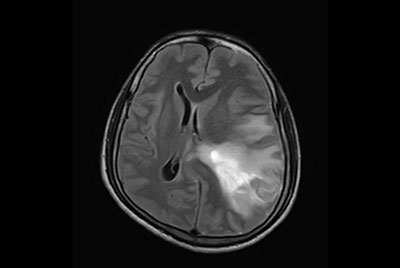

Multiple Sclerosis versus TIA

Brain Multiple Sclerosis

FLAIR* protocol for Multiple Sclerosis

Brain infarction